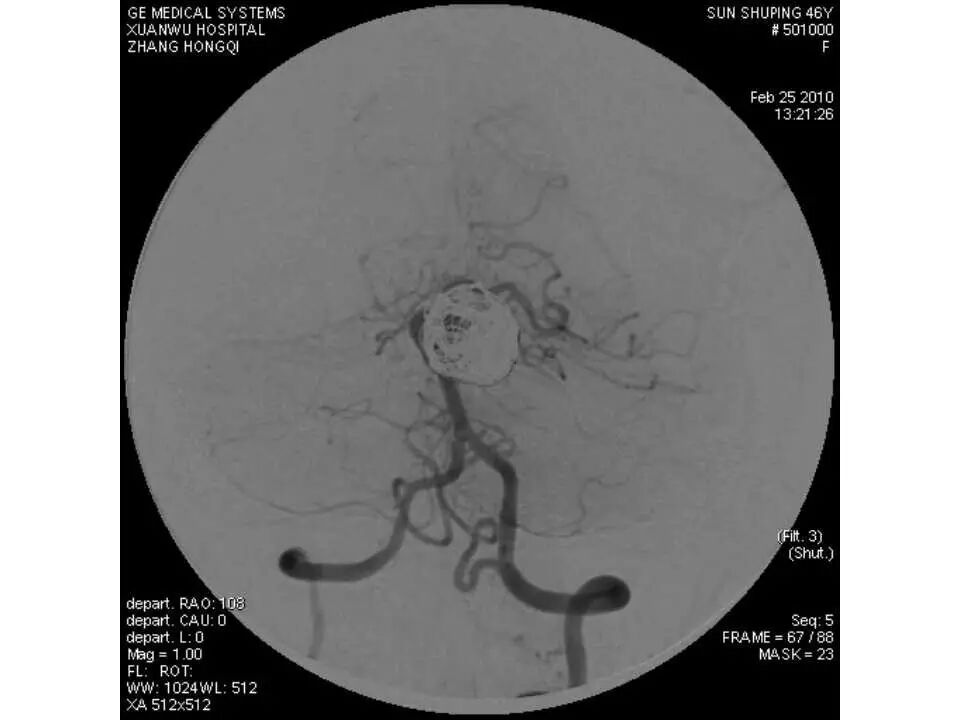

今天为大家分享的是“强生医疗CNV-神经介入专栏”第十五期,由首都医科大学宣武医院何川教授带来的“颅内动脉瘤介入治疗”精彩讲课视频及PPT,欢迎观看、阅读。文章仅代表作者个人观点,如有不同见解,欢迎同道斧正!